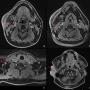

Initial computed tomograpgy neck showed extensive multiloculated gas containing collection seen at retropharyngeal region (red arrow) from the level of oropharynx in sagittal section

Case Report Page 551 - 556

Retropharyngeal Abscess with a Missed Migrating Foreign Body: A Case Report